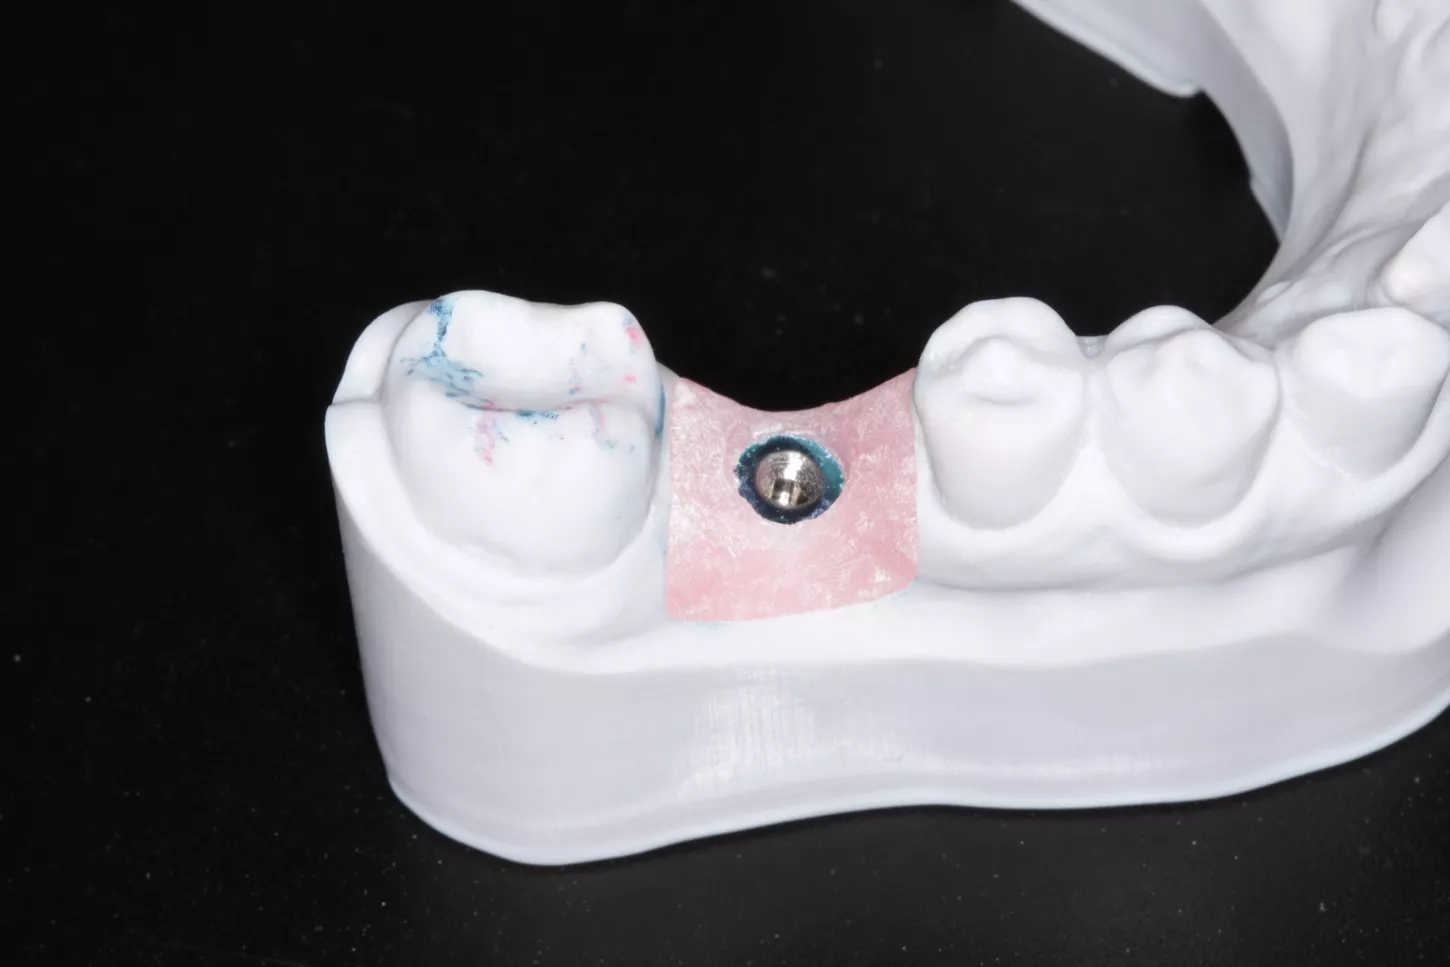

5a. 5b. Guide imprimé en 3D.

13. Maître modèle.